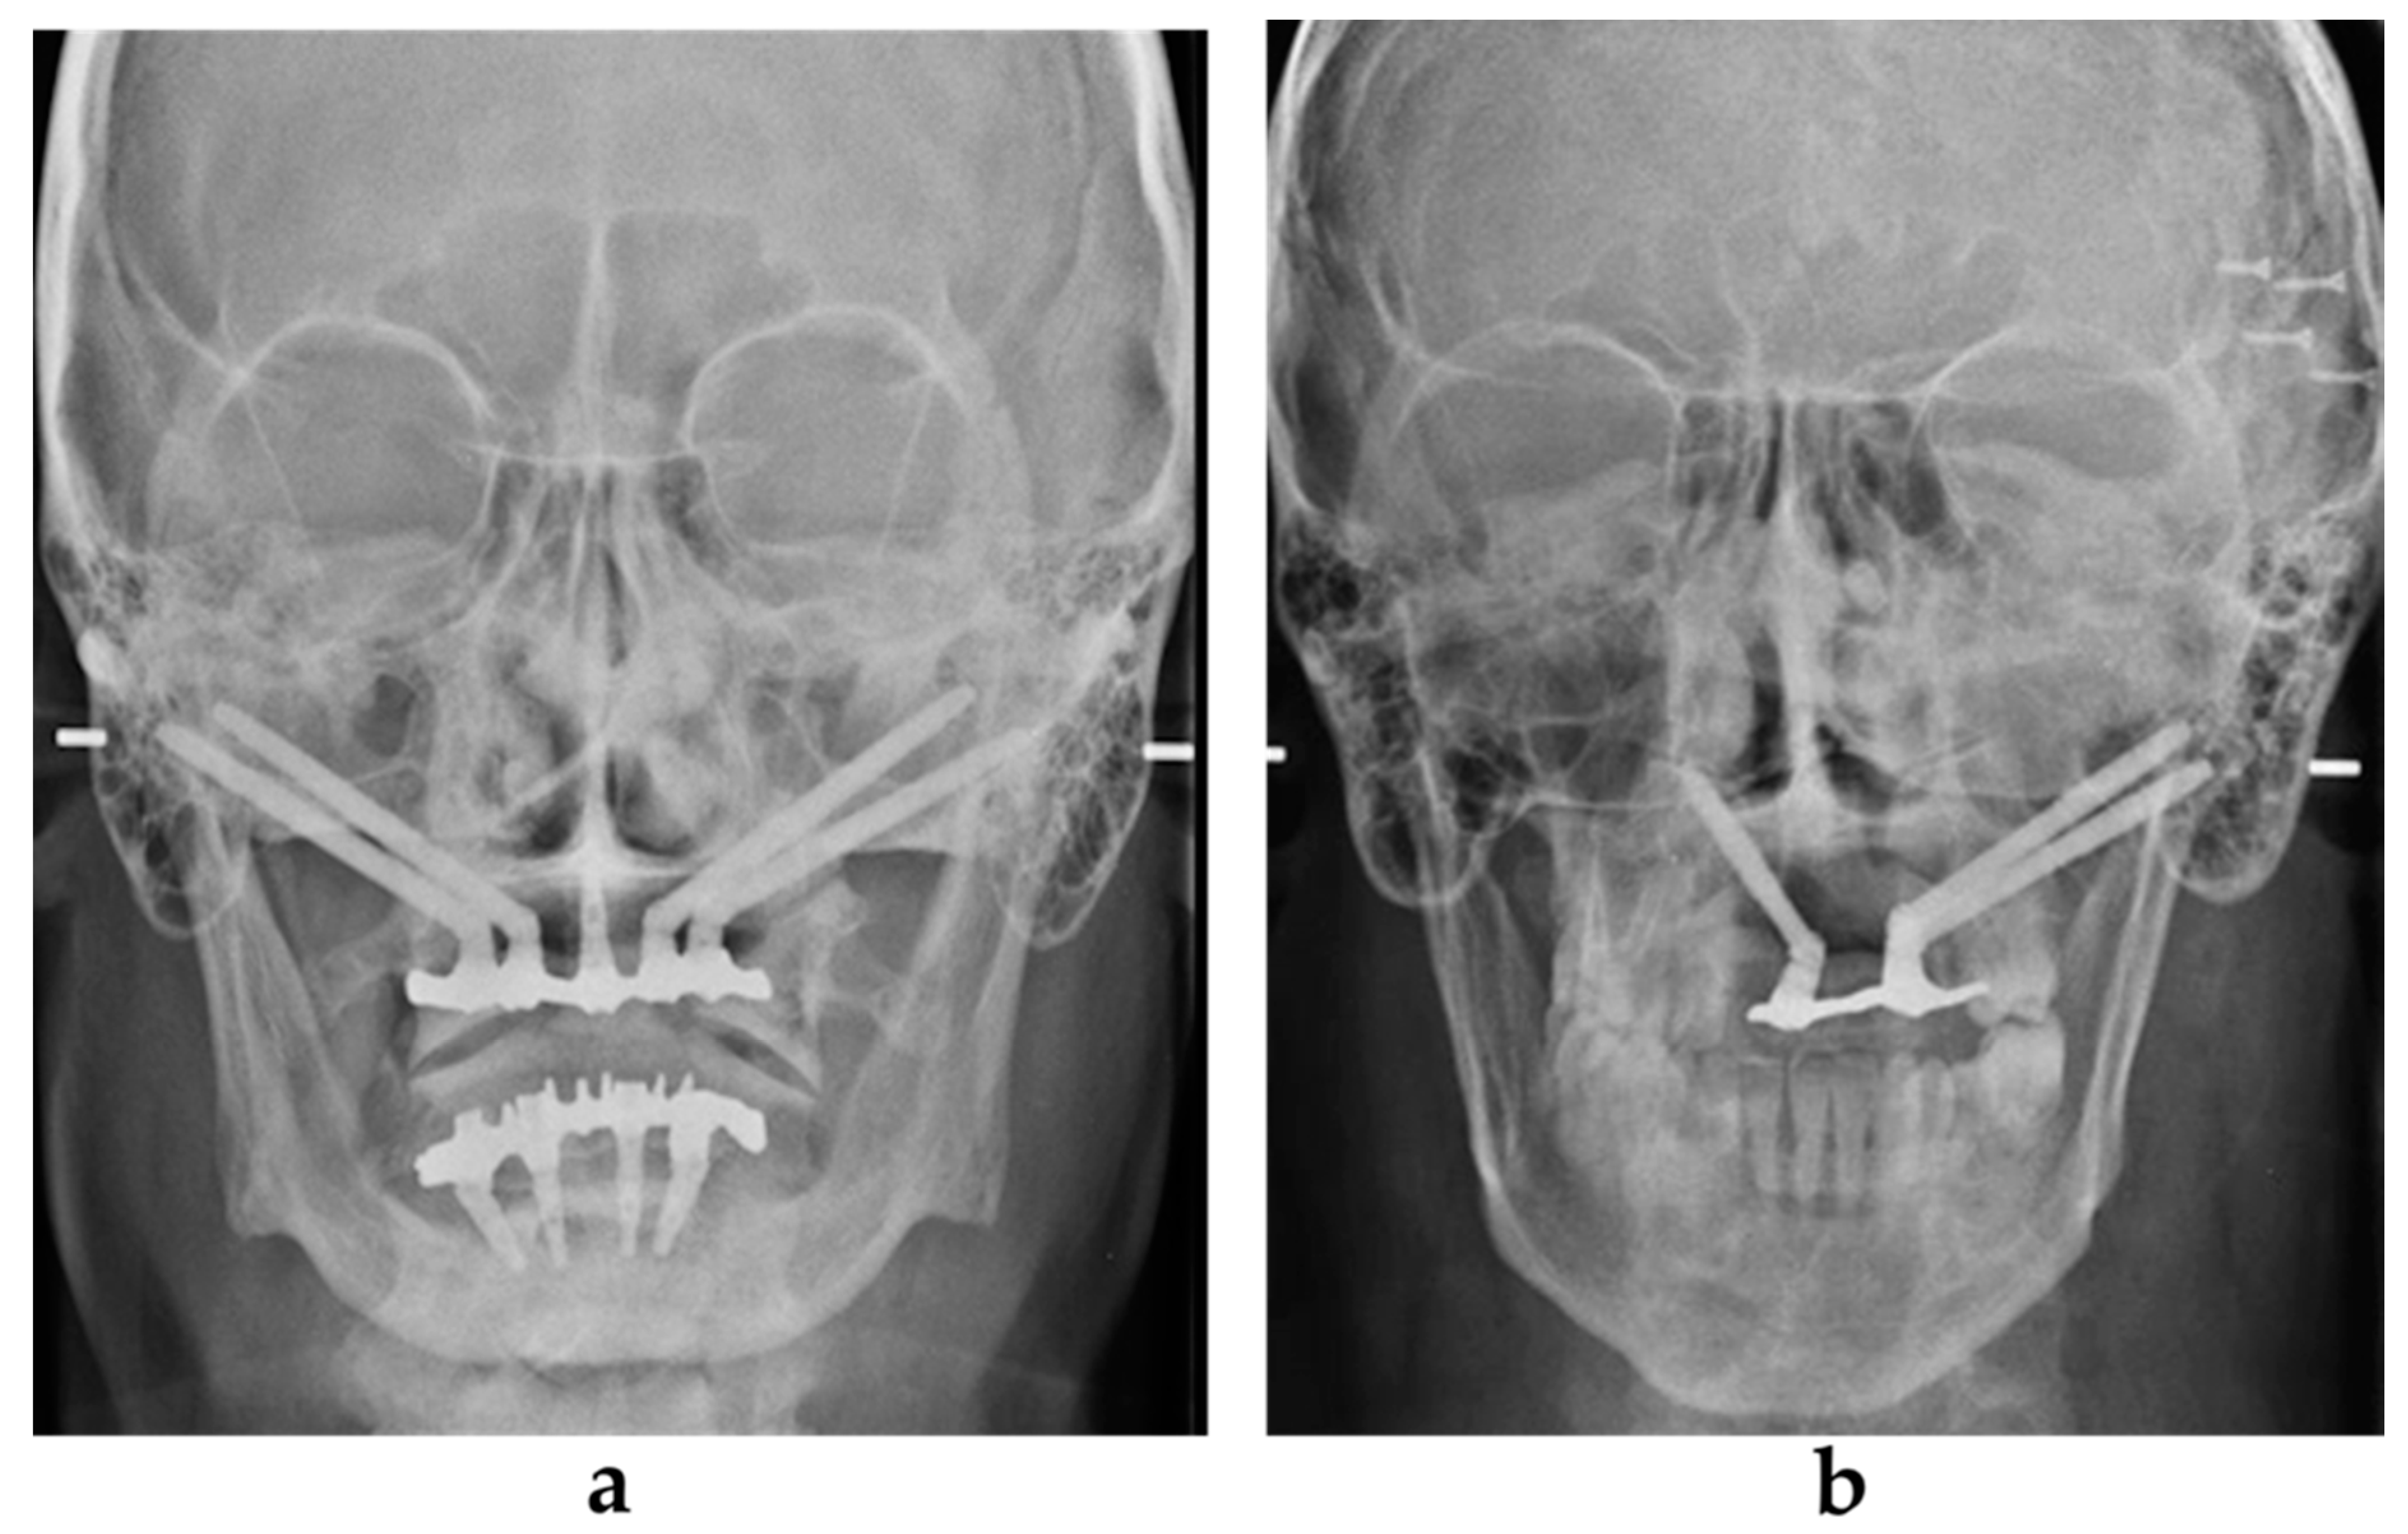

A maxillofacial type navigation system involving the use of an extraoral reference tool (onto the cranial bone) was employed in three oncologic patients in whom the residual maxillary bone was not sufficient for the fixing of the intraoral reference tool. After a final evaluation carried out by a depth gauge, zygomatic implants (Southern Implants, Irene, South Africa) were positioned via the use of implant motor or manually using a fixture mount. Standard zygomatic implants were placed in patients from the atrophic group and in oncologic patients when the implant collar was surrounded by the residual crestal bone (Figure 2a). The oncologic type of zygomatic implant was placed when there was only soft tissue around the implant collar (Figure 2b).

2.4. Prosthetic Procedure

Figure 2. The zygomatic implant was placed and the conical abutment was screwed before suturing. (a) The standard type of zygomatic implant was used for patients with maxillary atrophy. (b) An oncologic type of zygomatic implant with a machined coronal part was used for implant sites that lacked crestal bone.